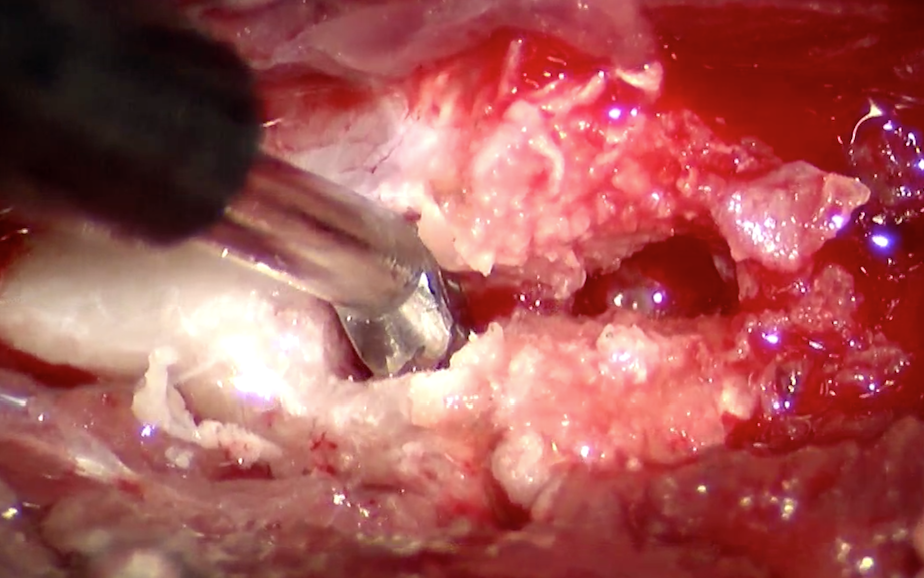

根治治療には逸脱した椎間板物質を摘出する必要があります。胸腰部の椎間板ヘルニアと異なり、頚部では腹側からのアプローチを用います(ベントラルスロット)。まず重要な組織である気管や食道、頸動脈静脈を避け、骨にアプローチします。骨の切削にはラウンドバーとよばれるドリルや、SonoCure(ソノキュア)とよばれる乳化吸引装置を用います。ソノキュアは骨だけを削り、神経や血管などの軟部組織は削れないという利点があります。

今回の症例では骨の幅が9mmであり、削る幅の最大経が3mmでした。それ以上の幅で削ると不安定性が出て合併症のリスクが高くなります。3mmの幅の内部での操作となるため、肉眼での操作は困難であり、顕微鏡操作が有用となります。以下は顕微鏡下での術野の視野になります。

骨をソノキュアによって少しずつ掘っていきます。

穴が深くなっています。

内部の白いものが椎間板物質になります。

椎間板物質を鉗子で摘出しているところです。